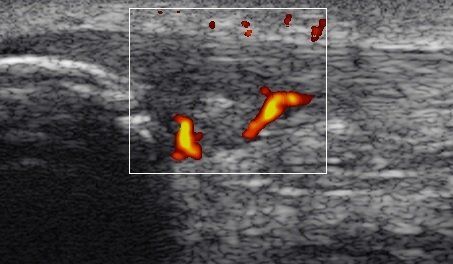

Imagem ecográfica de uma tendinopatia.

Quando existe uma neoneurovascularização no TA, na avaliação por imagem, podemos identificar a presença de Power Doppler positivo, ou seja, um sinal Doppler activo no lado ventral do TA. A neoneurovascularização pode ser definida como uma proliferação da rede nervosa e sanguínea (gordura de Kager’s), para o interior do tendão. Apesar de não existir uma associação absoluta entre dor e a neoneurovascularização intratendinosa, a evidência científica indica um nível de dor mais elevado em tendões hipervascularizados em comparação com tendões hipovascularizados.

Ecografia de uma tendinopatia rotuliana crónica e neoneurovascular

Nas tendinopatias degenerativas, para além da degradação de colagénio, degeneração mixóide, défice de mobilidade fluídica da matriz extracelular (MEC), e da morte celular, devemos considerar a importância de outra característica patogénica. Existe, de forma significativa, uma hipóxia (baixo teor de oxigénio), no tendão que provoca uma resposta inflamatória persistente.